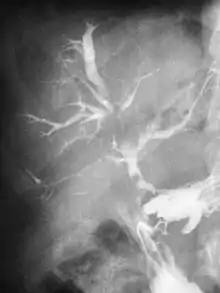

Abdominal CT scan with right colocutaneous fistula and associated subcutaneous pneumatosis | |